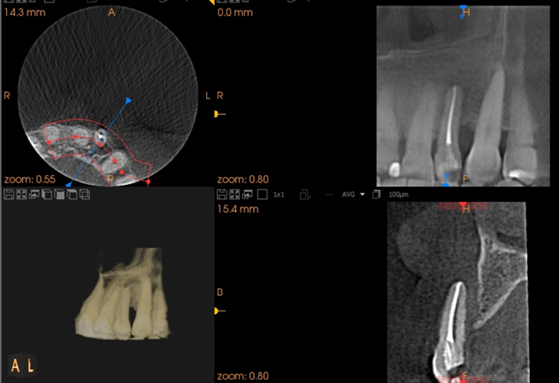

Nossa proposta é relatar o caso clínico da paciente M. S., que procurou a clínica do Curso de Especialização de Implantodontia da Universidade Paulista (Grupo Apoio) devido à condição do dente 22. Uma vez que a destruição periodontal era muito extensa, incluindo o ápice dental, foi indicada a exodontia do dente 22. Buscando reduzir o número de procedimentos cirúrgicos e o tempo necessário para a finalização do caso, foi realizada a reconstrução óssea imediatamente após a remoção do dente. Foi realizada a técnica de Regeneração Óssea Guiada (ROG) com membrana não absorvível de PTFE denso (Cytoplast), associada a enxerto ósseo xenógeno composto por 75% de hidroxiapatita e 25% de colágeno do tipo I (Extra Graft) (Vídeo 1 e Figura 3).

A escolha da técnica acima fundamenta-se no alto nível das evidências científicas associadas ao uso da associação da Regeneração Óssea Guiada (ROG) + substitutos ósseos xenógenos (Sanz-Sánchez et al., 2015), que garantem previsibilidade e bons resultados clínicos conforme demonstrado na Figura 8.

Após 8 meses da ROG, foi instalado um implante Cone Morse Due Cone 3,5 x 11mm através da técnica de cirurgia guiada por computador (Vídeo 2).